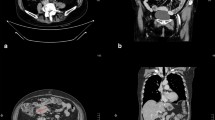

The sum of the diameters of target lesions (the smallest one for lymph nodes as per RECIST 1.1) was calculated for each patient's imaging. Let's denote Tpb and Spb, T0 and S0, TN and SN, and Teot and Seot, as the times of imaging and the sums of the target lesions at pre-baseline imaging, at baseline, at the nadir of response and at last study imaging, respectively. For patients not experiencing any tumour shrinkage, the nadir is considered to be the baseline. Tumour growth kinetics before the study treatment was evaluated for each patient by calculating the following slope: (S0−Spb)/(T0−Tpb). Tumour growth kinetics was also evaluated while on study treatment by calculating the following slope: (Seot−SN)/(Teot−TN) (Figure 1). The ratio of these two values was named the tumour growth ratio (TGr). Following classes were used to report the TGr: <0.7, 0.7–0.9, 0.9–1.1 and ⩾1.1. As an example, a TGr of 0.8 represents a 20% slow-down of tumour growth kinetics during study treatment as compared with before study treatment.